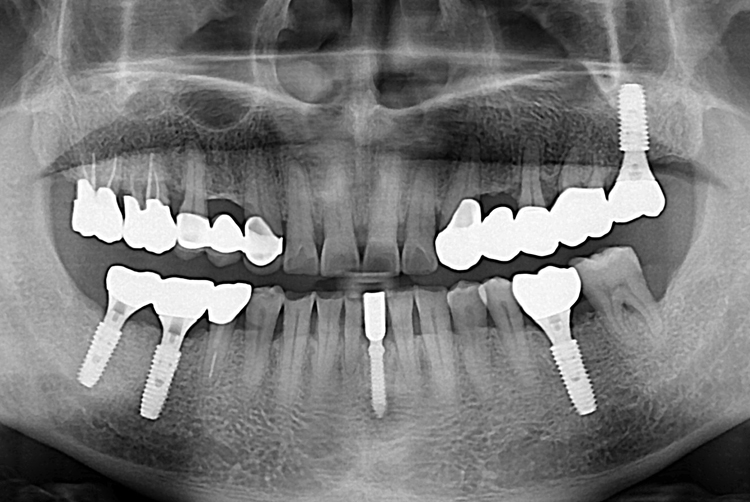

[임플란트] 앞니 임플란트

치료전 : 2019-08-16

치료후 : 2019-10-30

세종치과는 많은 환자와 다양한 케이스를 바탕으로

항상 편안한 임플란트 수술을 제공하고자 노력하고,

오래동안 튼튼히 쓸 수 있는 임플란트 수술을 가장 큰 목표로 삼고 있습니다.